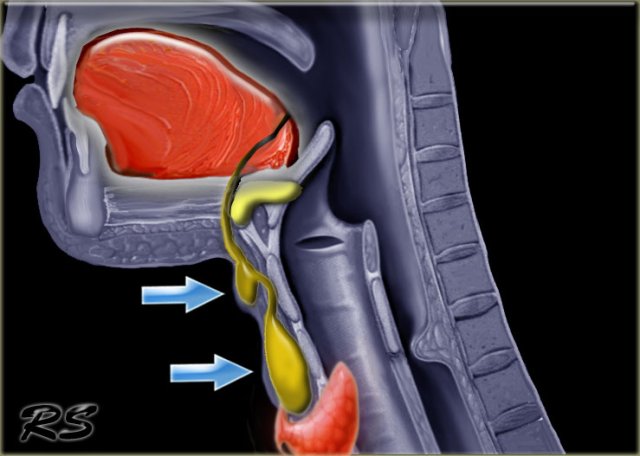

The thyroglossal duct runs from the base of tongue at the foramen caecum to the thyroid gland.

The embryonic thyroid gland travels through the duct to reach its final normal position.

Normally, the thyroglossal duct then involutes, but when the duct persists, a thyroglossal duct cyst can develop anywhere along this tract (figure).

Thyroglossal duct cysts move upward if the tongue is protruded or during swallowing (see next movie).